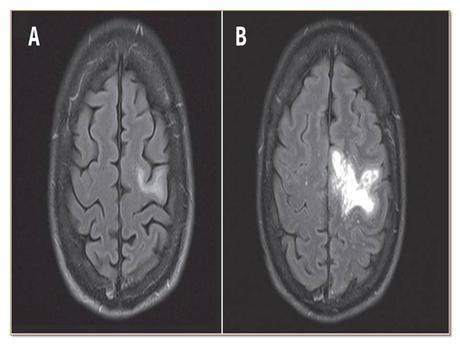

- Imaging tests: CT scan images show multifocal, non-contrast, hypo-dense lesions without mass effect. But MRI is more sensitive than CT scan.